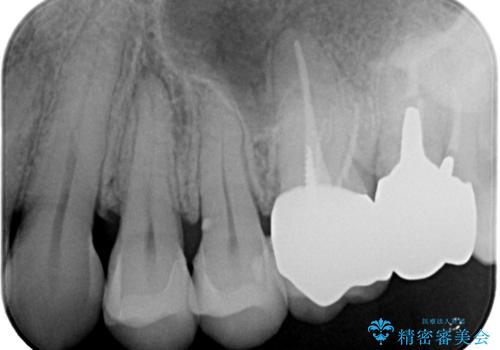

過去に装着されたメタルインレーを除去したのち、内部の虫歯を除去、セラミックインレーにて修復治療を行なっております。

e-maxプレスインレーを用いることで、高い精度と強度を達成することができました。